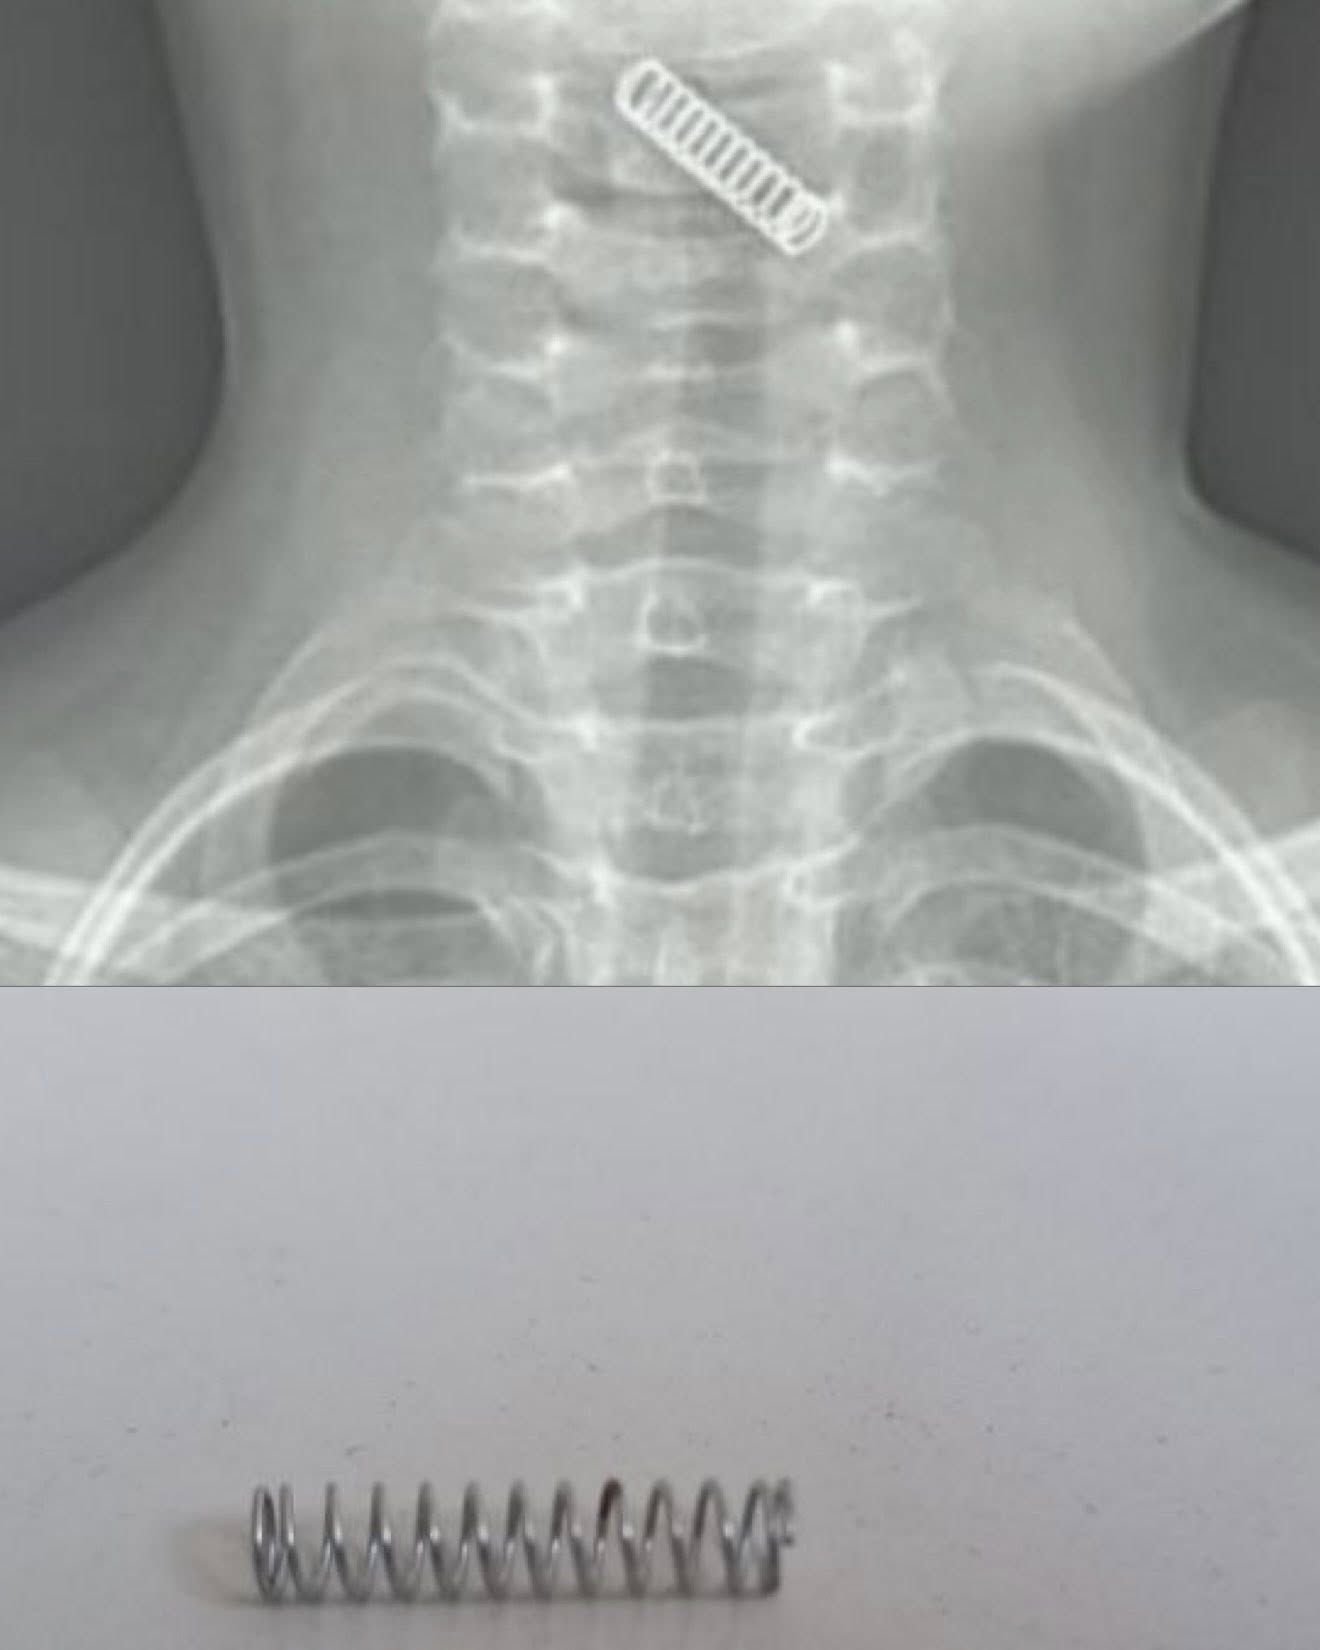

Діти переважно ковтають монети, батарейки, елементи конструктора LEGO і частини іграшок. Також були випадки, коли діставали стиральну гумку та деталь від викрутки.

У "колекції" медиків також пульпоекстрактори від стоматологів, канцелярські цвяхи та лампочки з ялинкових прикрас. Інколи діти вдихають навіть власні молочні зуби.